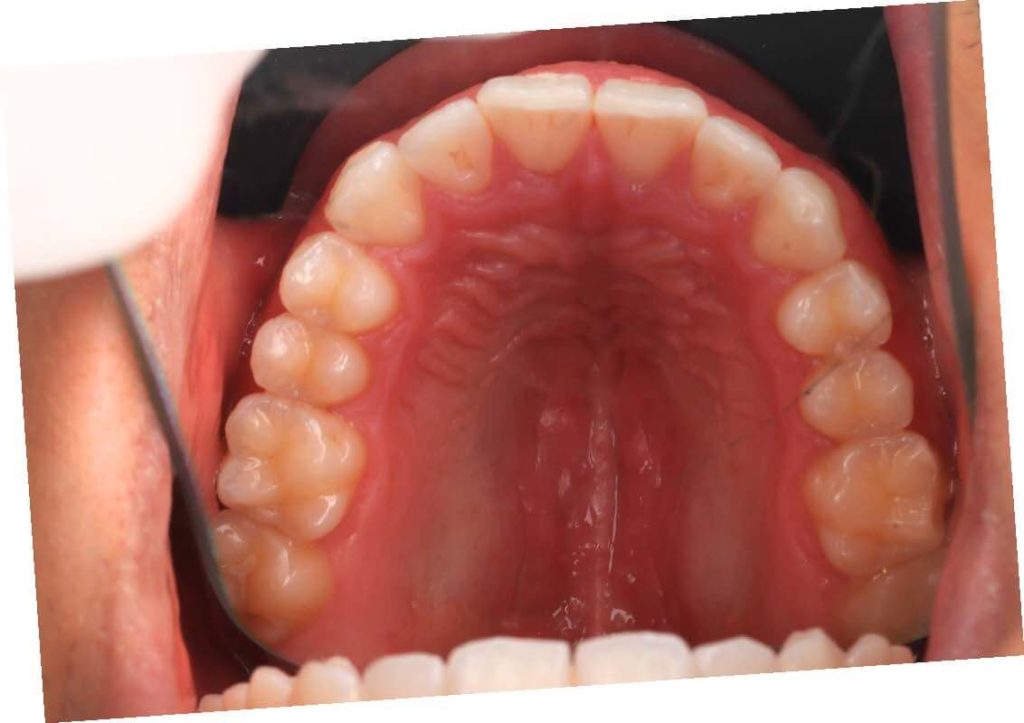

SITUACIÓN INICIAL

CLASE I MORDIDA CRUZADA EN LATERALES

• Clase I con mordida cruzada en los incisivos laterales.

• Apiñamiento moderado en el arco superior e inferior.

• Desplazamiento de la línea media superior.

• Arco normal con necesidad de expansión.